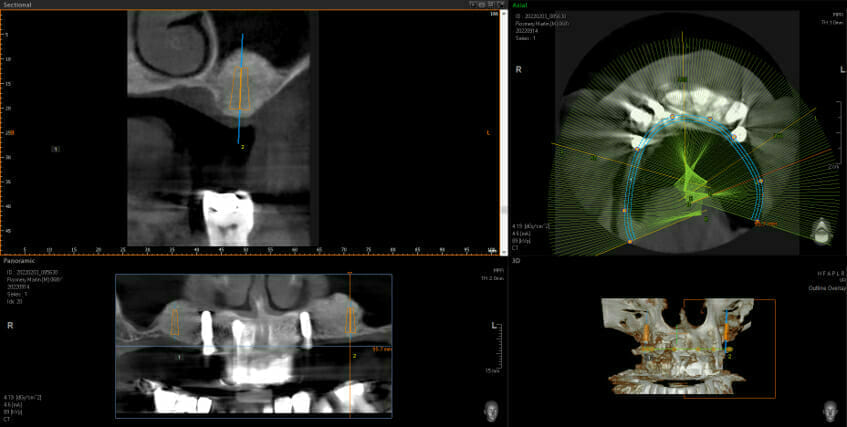

This shows big black areas where the sinuses are and shows that there is not enough bone to put the implants in (shown in orange). You don’t have to be an implantologist to see how much bone we have after the grafting. Now we can go ahead and place 2 implants each side at the back and this allows the addition of 3 new back teeth each side (using implant bridges means we still only need 4 implants, not 6, keeping surgical complication and costs down)

Before Sinus Bone Grafts

After Sinus Bone Grafts with 2 out of the 4 implants in place